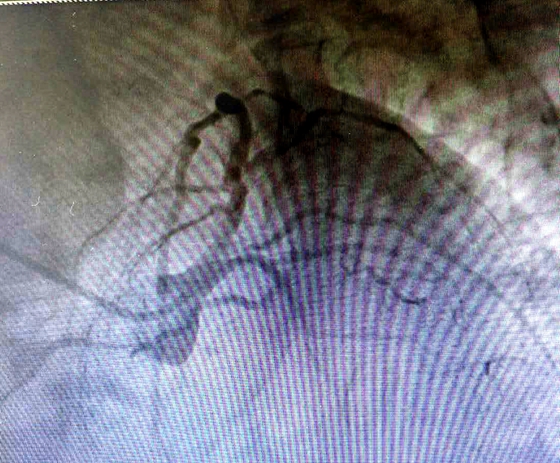

近日,湘雅常德医院心血管内科为一名冠脉严重钙化病变的患者成功实施冠脉旋磨术。 今年63岁的李某,5年前开始反复出现胸闷气促,活动后加重,休息后可逐渐缓解。后因症状逐...